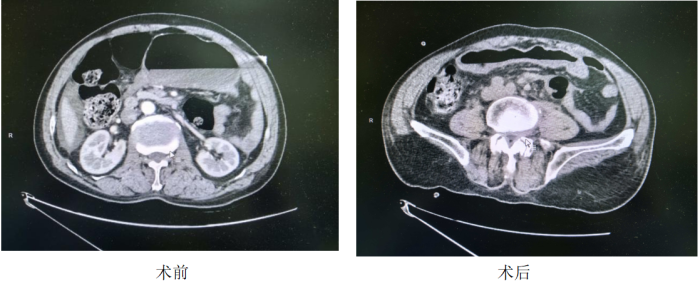

该患者为老年男性,因严重脑外伤在思南县人民医院神经外科住院手术治疗,期间突发腹胀、腹痛、呕吐及肛门停止排气排便,急诊腹部CT确诊为乙状结肠扭转,扭转角度超180度,伴肠管明显扩张。

术后患者症状迅速缓解,复查CT提示肠扭转消失,肠道功能逐步恢复,目前病情稳定。此前此类重症患者需转往上级医院,转运风险极高,此次突破实现了县级医院急危重症精准微创救治,填补了全县内镜下急腹症重症救治的空白。